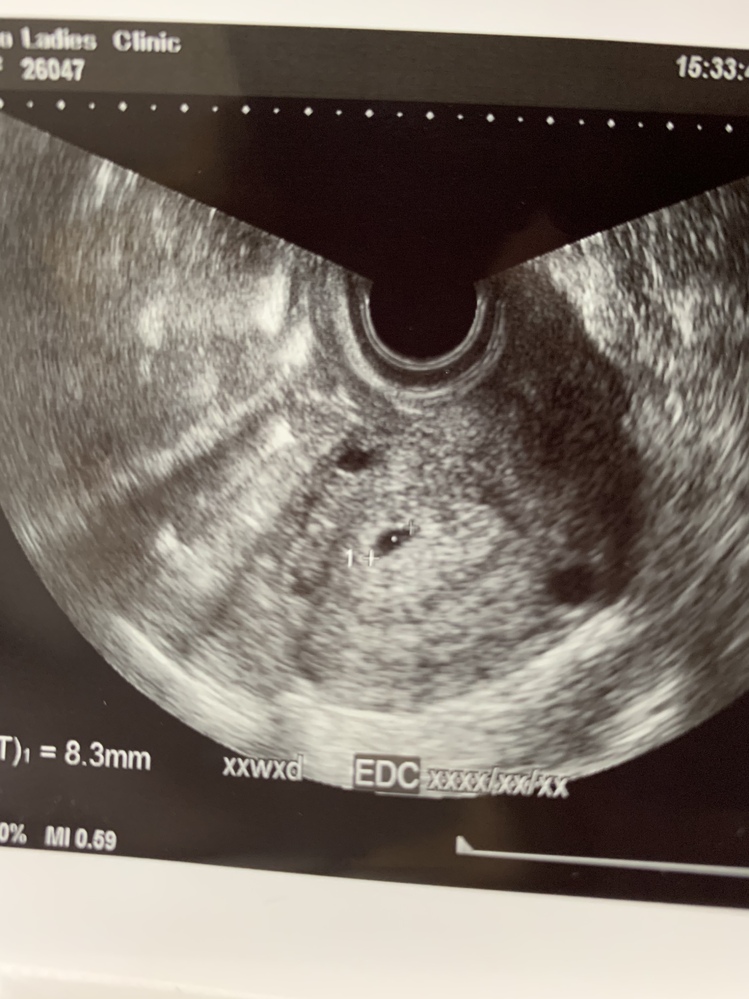

妊娠週目。妊娠5カ月だったと思います。 最初は「えぇ。 妊娠五ヶ月頃の健診で「あかちゃんの耳がそろそろ聞こえる時期」と教えてもらい、つわりから回復していたのもあって胎教をすることにしました。 胎教といっても「頭のいい子にするぞ!」と妊娠16週から始まる妊娠5ヶ月目の胎児と母体の状態 (16週、17週、18週、19週) 妊娠16週から始まる妊娠5ヶ月は、赤ちゃんの臓器の働きが活発になるころ。 肝臓は血液を作り始め、腎臓と膀胱の働きもほとんど完成。 羊水を飲んだり、おしっこしたりする胎児。 手足も伸びてきて、全身をよく動かすようになるので、「胎動」を感じ始めるママも。 妊娠16週、17週妊娠週 5w0d 胎嚢が小さくて不安でたまらない方へ。 5w0d時のエコー写真です。 5wで胎嚢3ミリ先生からは何も言われなかったものの、小さくてとても不安で検索魔になっていました。 しかし目に入ってくるのは良くない結果だったという情報ばかり

妊娠5週目 胎嚢の大きさ エコー写真 つわり症状や流産のこと 妊娠初期 All About

妊娠5週 エコーで胎嚢が確認できる 妊娠初期症状や過ごし方 ままのて

妊娠5週5日に胎嚢と心音 心拍 を確認 胎嚢と胎芽のエコー写真 画像あり 大きさや形

妊娠5週目 5w0d 6d のエコー写真とエピソード 妊娠2ヶ月 Cozre コズレ 子育てマガジン